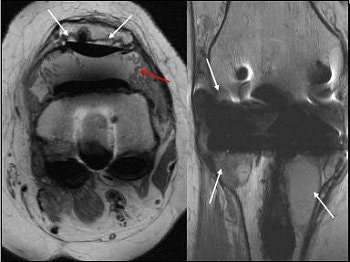

![]() |

Above, 68-year-old female who underwent TKA in 2001. Extensive particle disease, suspected split through the polyethylene at the posteromedial margin of the tibial tray and diffuse resorption of bone around the femoral component, indicative of loosening. Middle and below, TKA with large burden of particle disease (red arrow), which caused loosening of the patellar backing (white arrows). All images courtesy of Dr. Douglas Beall.